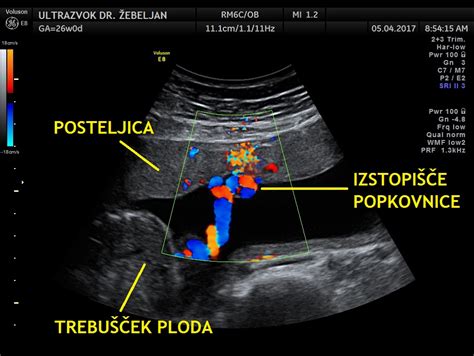

- Posteljica in popkovnica: Ocenjuje se lega in debelina posteljice (v tem obdobju je debelina v milimetrih enaka tednom gestacije). Pregleda se tudi vstop popkovnice v posteljico. Popkovnica v prečnem prerezu prikazuje dve arteriji (manjši žili) in eno veno (večja žila), ki ju ščiti Whartonova žolca.